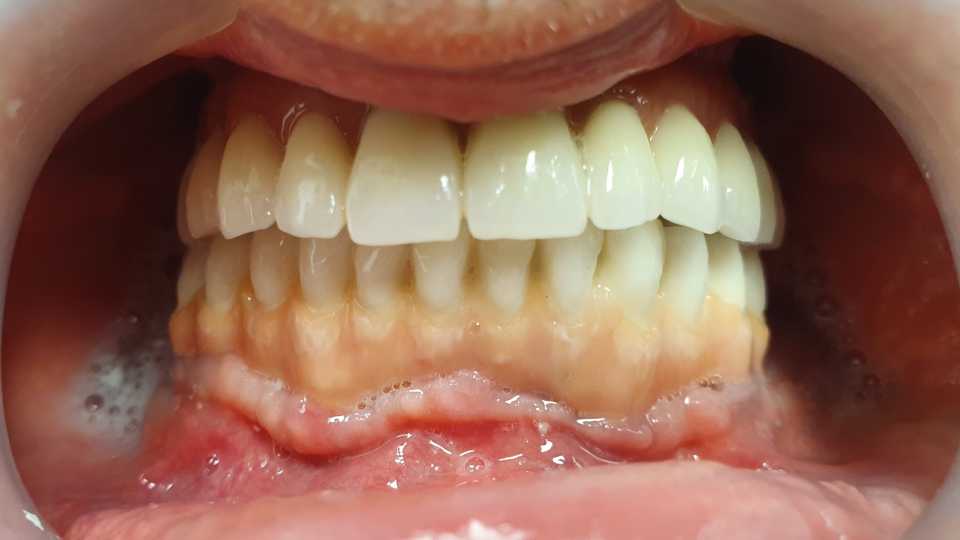

Pacientul a revenit in cabinet pentru consultatia anuala de intretinere, implanturile fiind inserate in urma cu 5 ani.

Cazul a fost unul foarte dificil pacientul fiind purtator vechi de proteze totale acrilice bimaxilar. A fost nevoie de 2 sinus lifting-uri si 5 implanturi pentru arcada superioara, iar pentru arcada inferioara s-au realizat aditii osoase (bilateral), prin tehnica Khoury.

Rezultatele au fost spectaculoase, fara sa fi intervenit resorbtii de natura osasa sau gingivala, pacientul fiind foarte multumit.